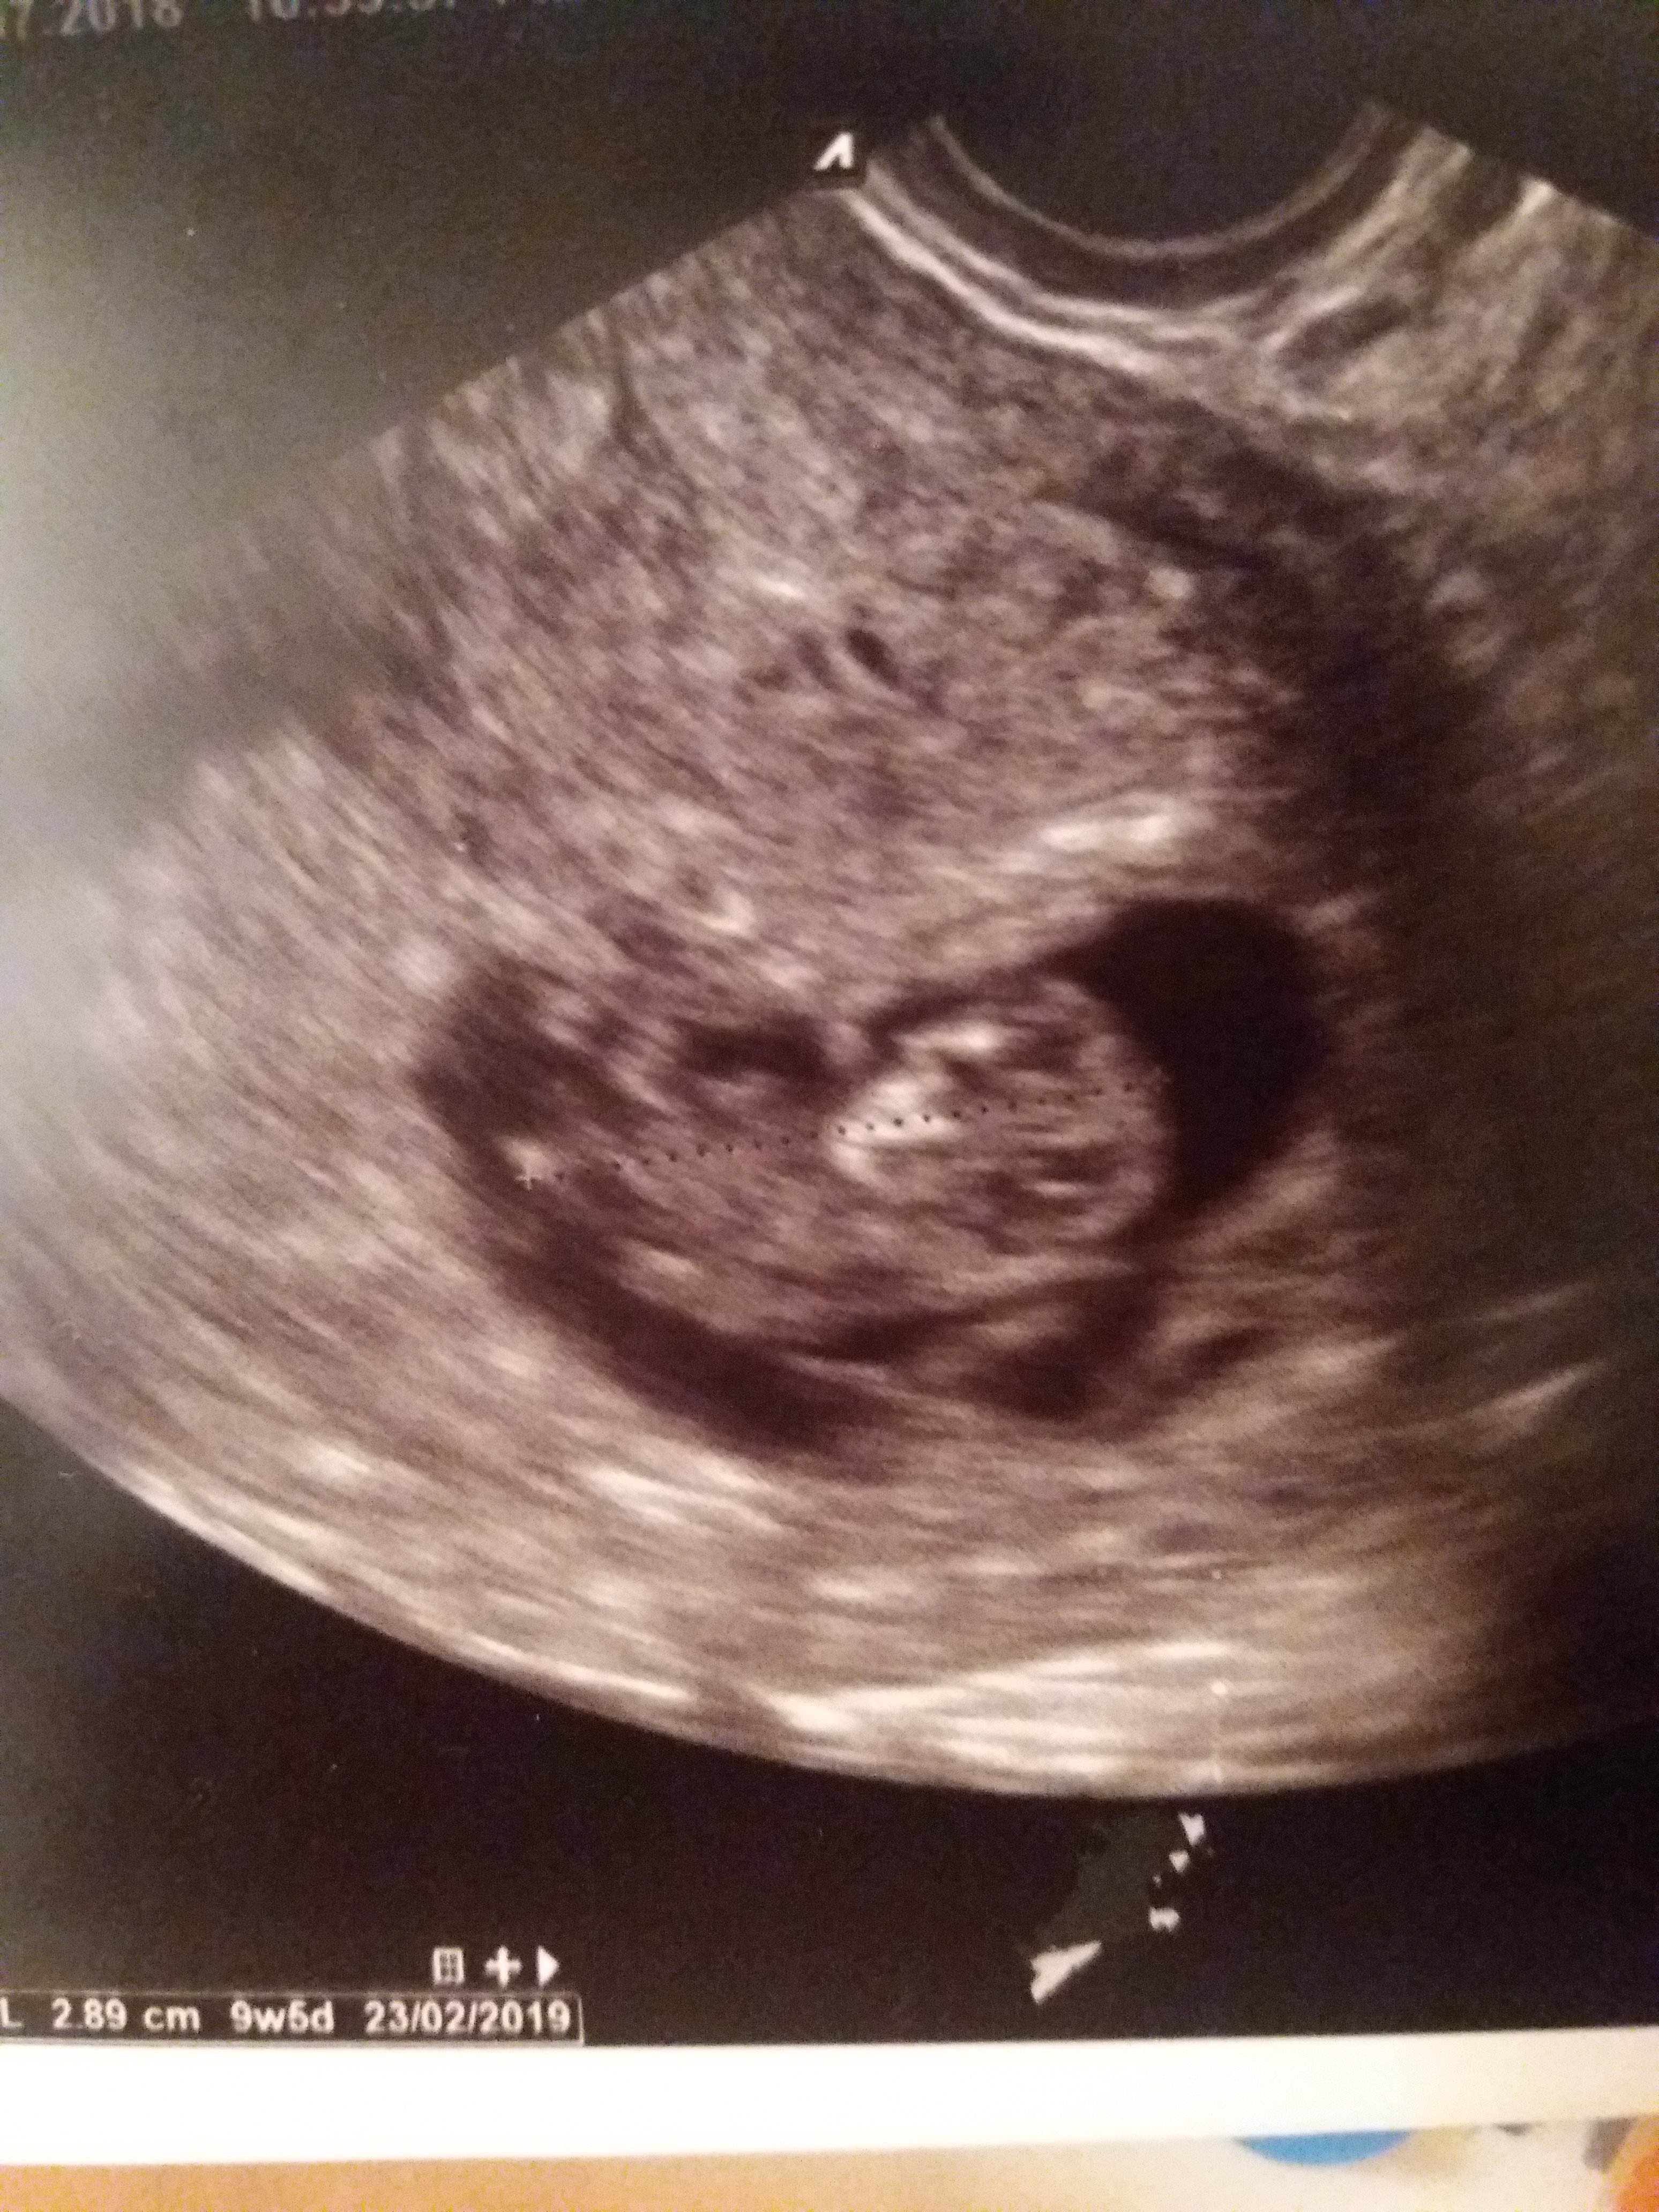

Ja już po wizycie. Krwiak jest dalej ale jak to lekarze mówią organizuje się. To znaczy podobno trochę zmalał i robi się jasny więc lekarka mówi, ze wszystko jest na dobrej drodze. Nic się nie odkleja kosmowka ani nic więc lekarka jest dobrej myśli.

I dzidziuś sporo urósł z 1,1 cm do 2,9 cm

Już na USG jak czlowieczek wygląda !

Wg USG to 9t5d a według okresu 10t5d ale lekarka mówi,ze taką różnicą może być.

Ale trzymamy się terminu wg okresu czyli 17.02